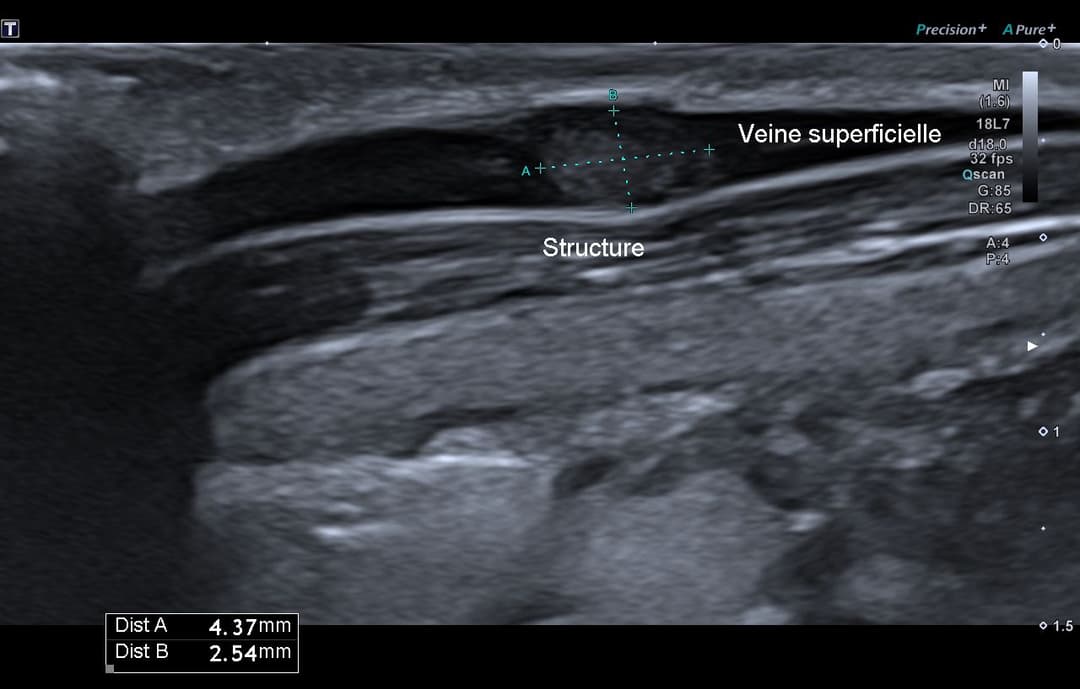

Échographie

Matériel échogène tissulaire endoluminal dans une veine superficielle collatérale de la veine jugulaire externe droite, présentant un pédicule vasculaire en Doppler couleur.